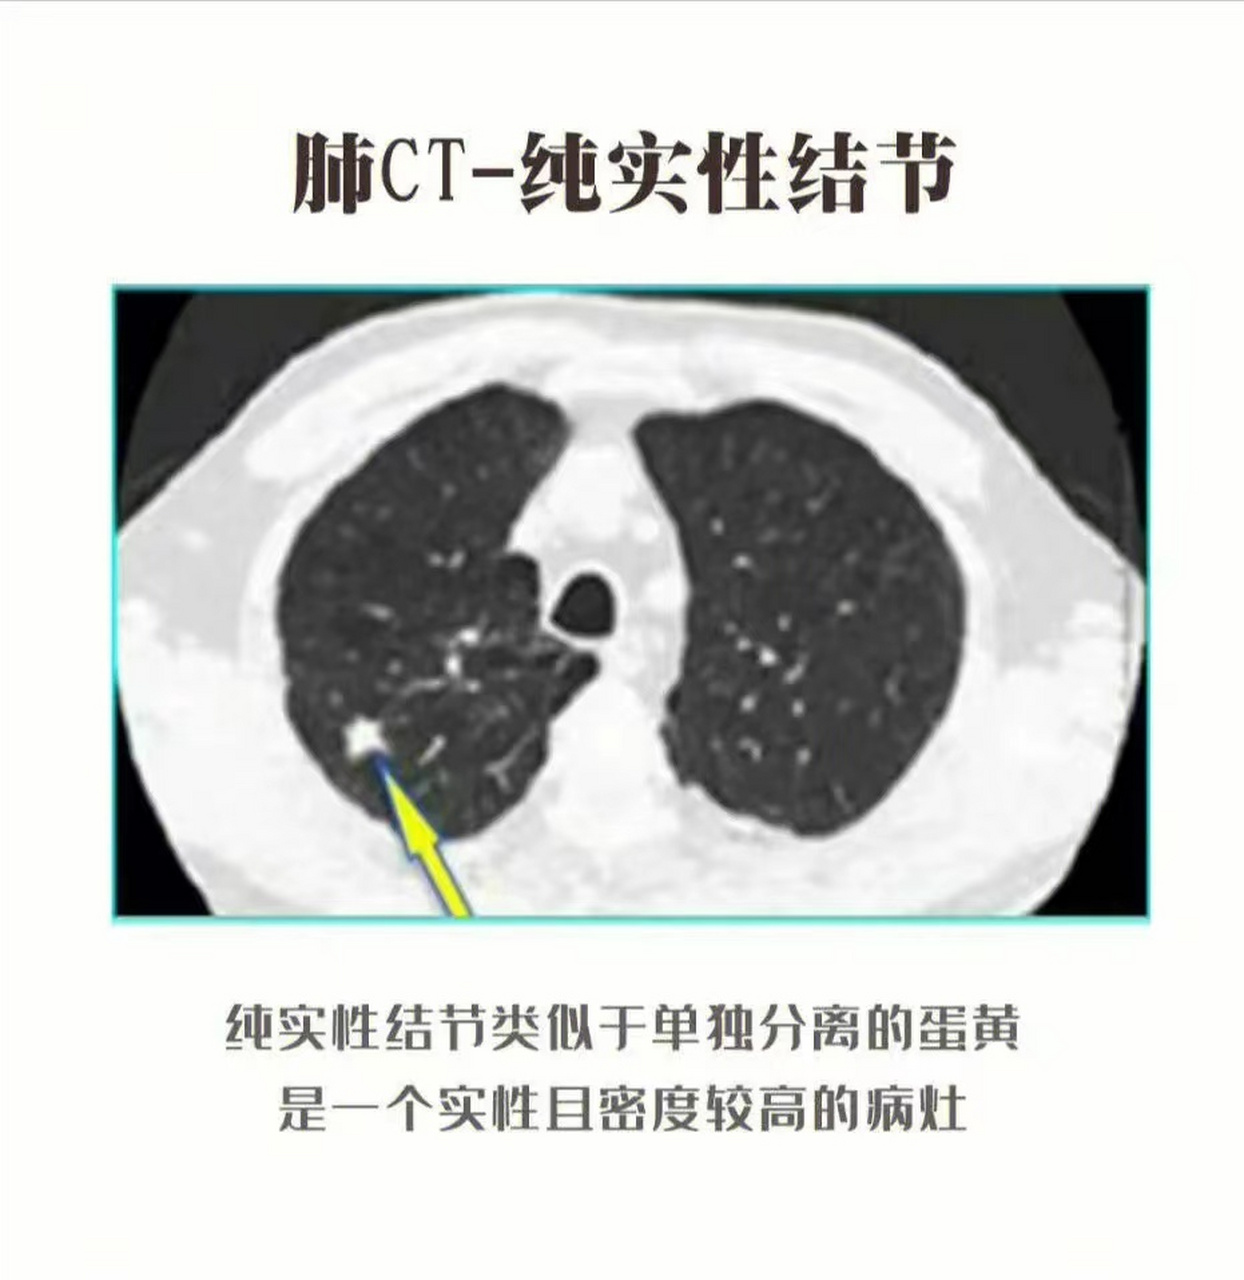

实性肺结节的恶性征象,跟混合磨玻璃结节有很多重叠: 1,分叶毛刺 2